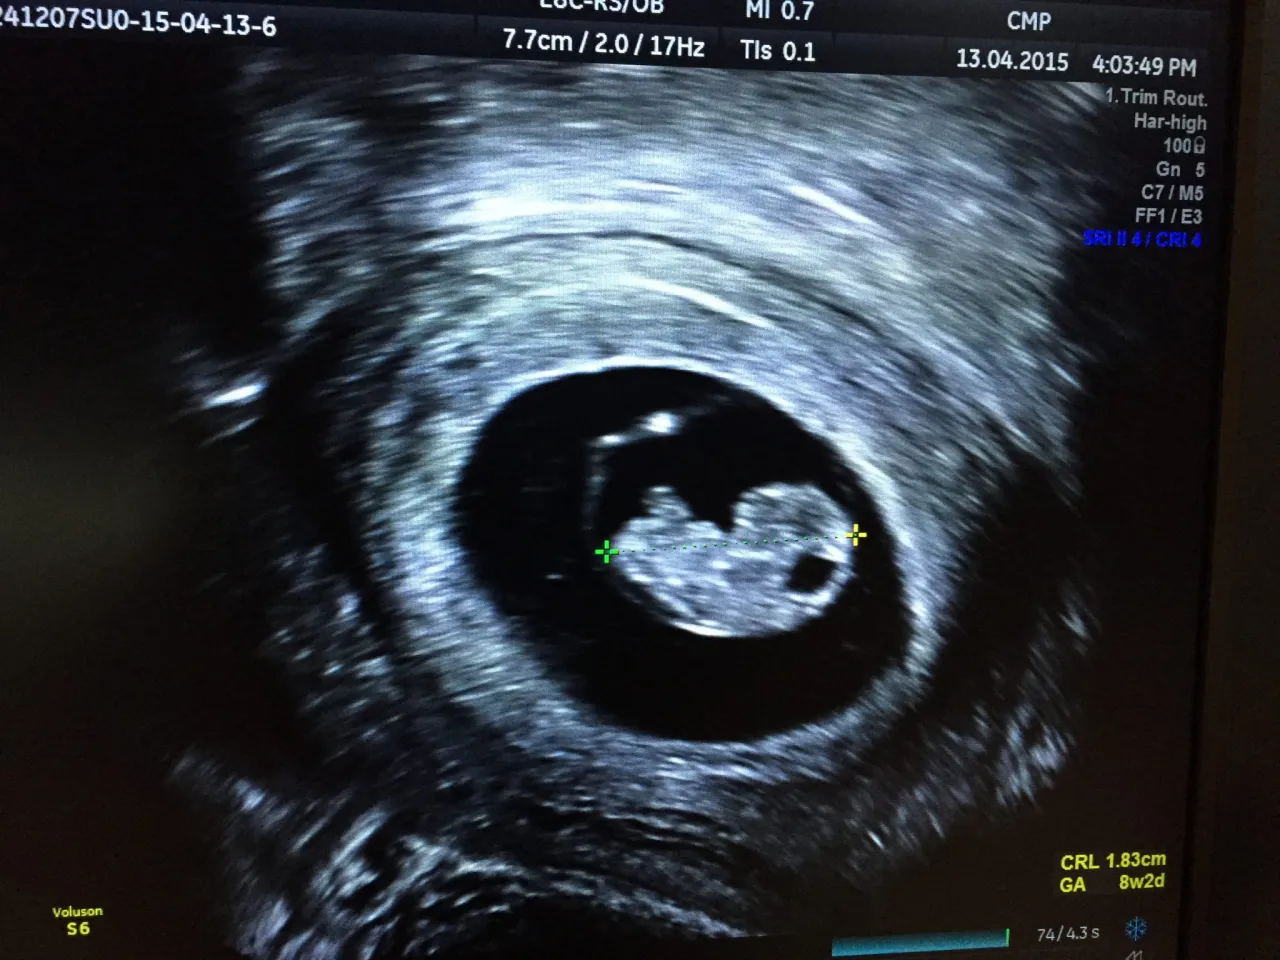

Co mierzy lekarz podczas badania, czyli tajemnicze CRL

Podczas badania USG w pierwszym trymestrze lekarz mierzy tak zwaną długość ciemieniowo-siedzeniową (CRL Crown-Rump Length). Jest to pomiar długości zarodka od czubka głowy do końca tułowia (bez nóżek). CRL jest niezwykle precyzyjnym wskaźnikiem wieku ciążowego, ponieważ w tym okresie zarodek rośnie bardzo szybko i w przewidywalny sposób. Na podstawie tego pomiaru specjalistyczne oprogramowanie USG automatycznie oblicza aktualny tydzień ciąży i przewidywany termin porodu. To właśnie ten wynik jest dla mnie najbardziej wiarygodny.

Zdarza się, że data porodu wyliczona na podstawie ostatniej miesiączki różni się od tej ustalonej przez USG. Jeśli ta różnica wynosi więcej niż 7 dni, to właśnie data określona na podstawie badania USG w pierwszym trymestrze staje się datą wiążącą. Jest to standardowa procedura w opiece prenatalnej. Dlaczego? Ponieważ, jak już wspomniałam, wczesne USG jest dokładniejsze, szczególnie w przypadku nieregularnych cykli, późnej owulacji lub błędnego zapamiętania daty ostatniej miesiączki. Pamiętaj, aby zawsze informować lekarza o obu datach, aby mógł podjąć najlepszą decyzję.